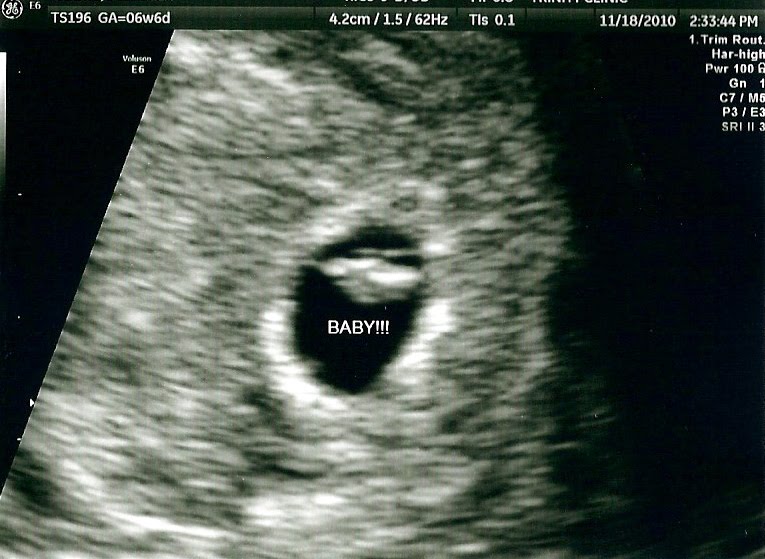

So yeah...Here is our first ultrasound picture of Spud -- a nickname James gave the babe. Healthy with a heart rate of 114.

Grow, Baby, Grow!